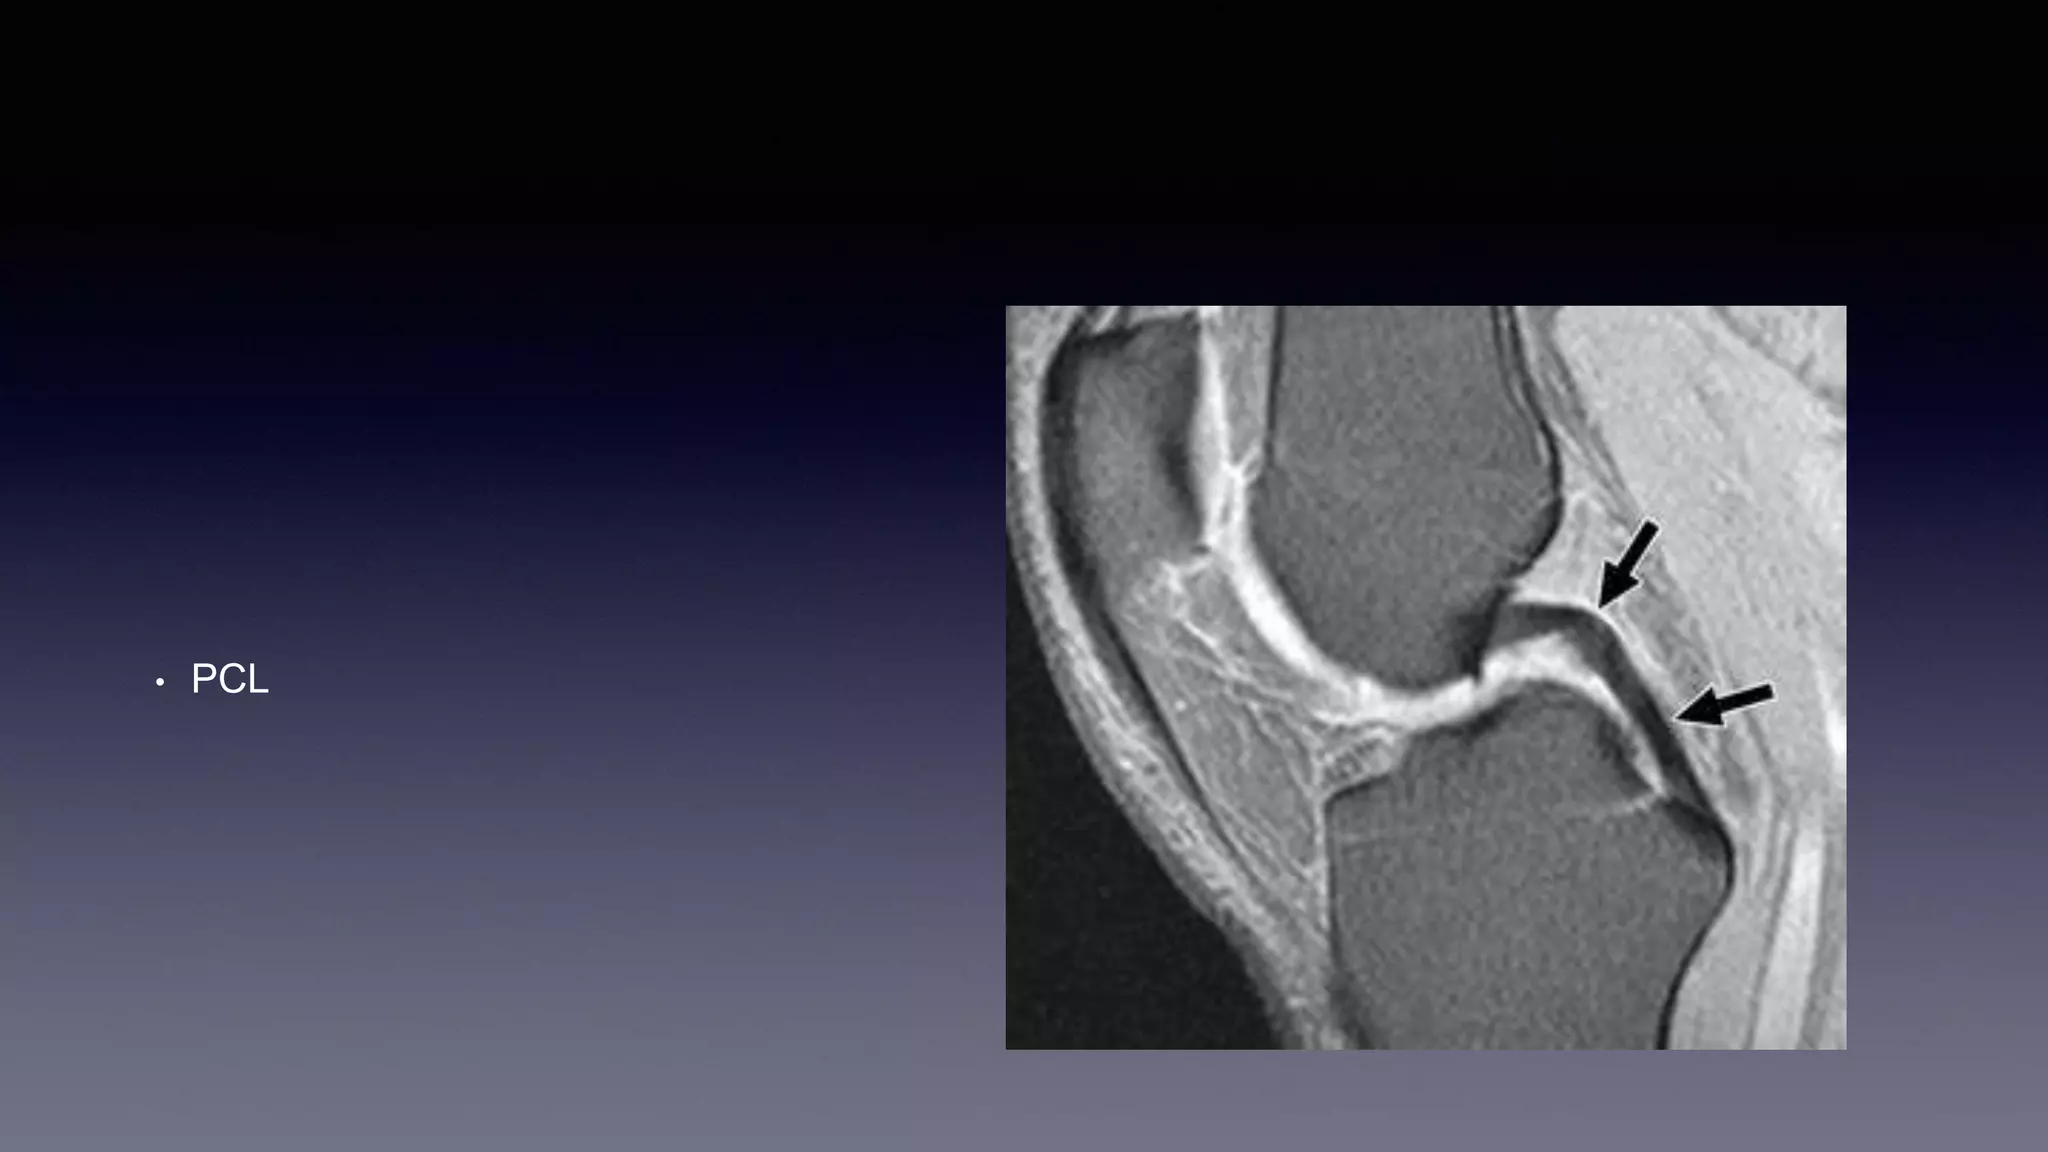

This document discusses using MRI to diagnose ligament injuries in the knee. It begins with an overview of MRI anatomy of the knee and expected pathology. It then discusses specific ligaments like the ACL, PCL, MCL and LCL. For the ACL, it shows images of acute tears, chronic tears and intrasubstance tears. It emphasizes knowing the knee anatomy well and correlating any abnormalities seen with clinical findings in order to apply the appropriate treatment.